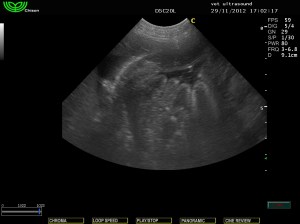

Στοιχεία ουραιμικής γαστρίτιδας

( λόγω αύξησης της ουρίας στον ορό του αίματος)